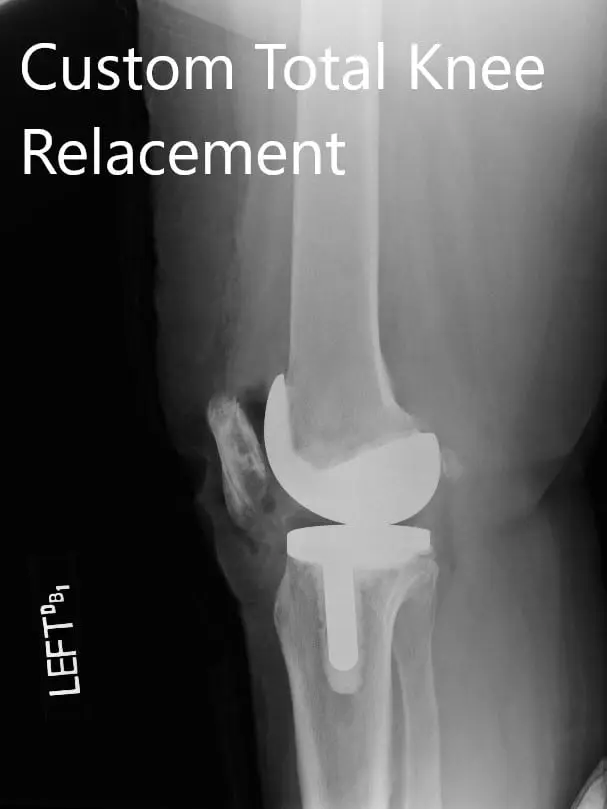

Postoperative X-ray images showing the AP and lateral views of the left knee

Post-op weight-bearing was started on the same day of the surgery. He was able to walk for 50 feet. The pain was well controlled with medications. Aspirin 325mg BID was started for DVT prophylaxis.

The patient demonstrated a full range of motion of the left knee. Physical therapy focusing on muscle strengthening and flexibility was continued. After 2 months, the patient was happily driving his car, performing his daily activities and brought a picture of him playing golf. He follows up as needed.